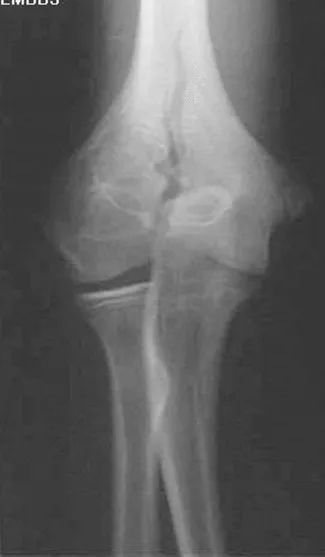

肱骨髁上骨折

肱骨髁间骨折